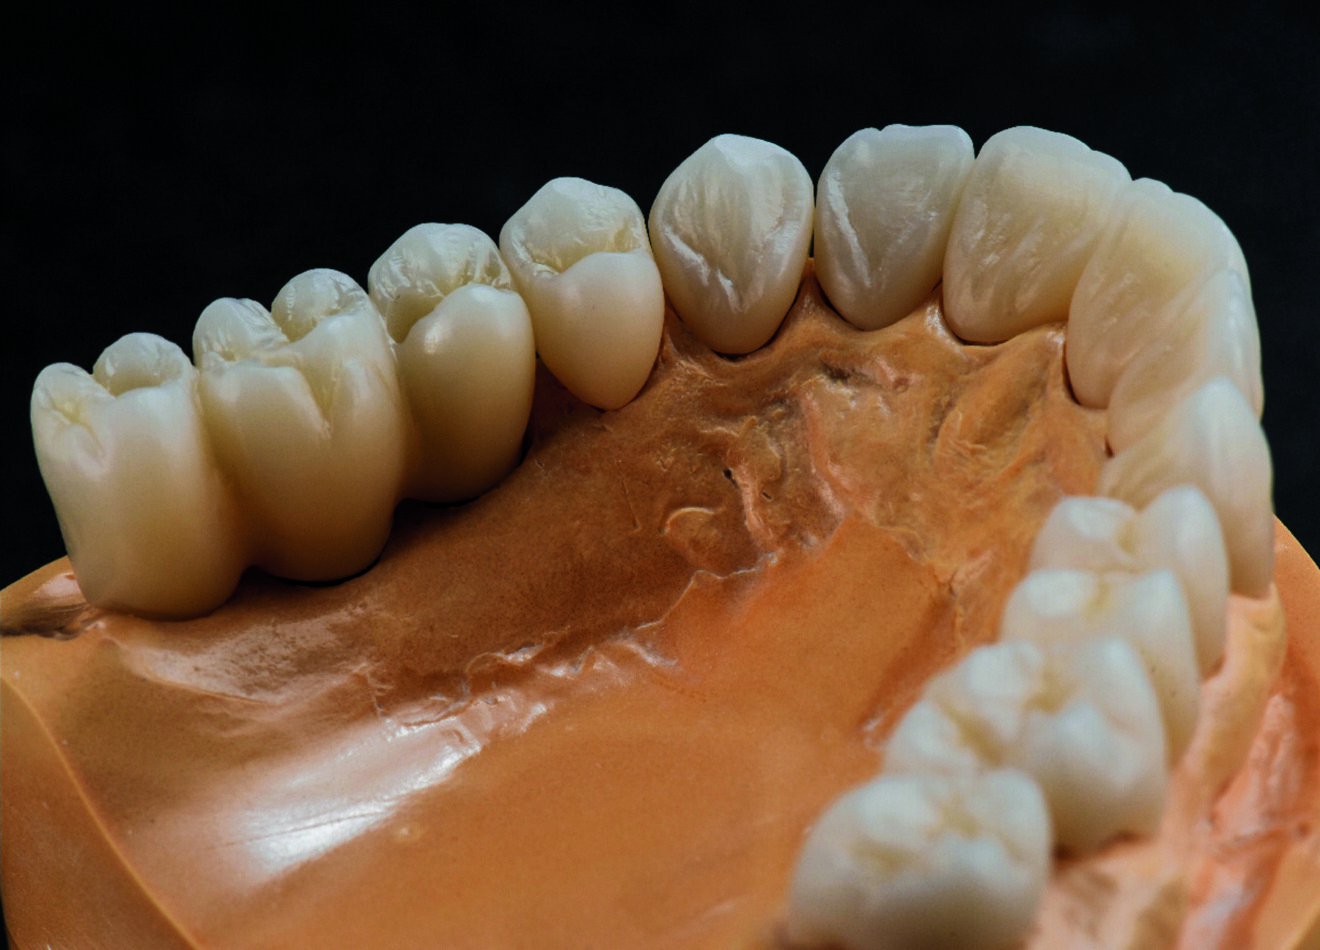

Fig. 6a : Magnifiques résultats après le traitement de surface manuel.

Fig. 6b : Magnifiques résultats après le traitement de surface manuel.

L’usineuse Ceramill Motion 2 (Amann Girrbach) donne des résultats de fraisage très satisfaisants, mais si je veux obtenir une structure de surface plus détaillée et beaucoup plus esthétique, je prépare les surfaces manuellement. Je choisis soigneusement mes outils, car il est essentiel d’éviter des éclats et des fissures dans la zircone, ainsi que toute contamination, au cours de cette procédure (Figs. 6a et b). Le traitement de surface manuel permet d’obtenir de magnifiques petits détails et des formes d’apparence naturelle, notamment les périkymaties et les crêtes transversales, qui sont inhérentes à la morphologie des dents antérieures.

Après le frittage, je dispose ainsi de la base parfaite pour passer à la phase de finition (Figs. 7a et b). Les contacts occlusaux sont polis à la main avant le glaçage, puis j’ajoute les dernières touches de colorants et de glaçures, pour créer un brillant naturel. Selon moi, le plus grand avantage de Zolid FX Multilayer est la possibilité de reproduire précisément la forme conçue numériquement. Ce que je souhaite est en effet de réduire au maximum le besoin de retouches après le traitement, surtout dans les cas complexes (Figs. 8a et b).

Fig. 7a : La structure de la surface est encore visible après le frittage.

Fig. 7b : La structure de la surface est encore visible après le frittage.

Fig. 8a : Dernières touches de colorants et de glaçures qui ont permis l’obtention d’un brillant naturel.

Fig. 8b : Dernières touches de colorants et de glaçures qui ont permis l’obtention d’un brillant naturel.

Fig. 10a : Résultat hautement esthétique et fonctionnel.

Fig. 10b : Résultat hautement esthétique et fonctionnel.

L’aspect fonctionnel est une partie importante de ma tâche journalière au laboratoire, et la combinaison du traitement virtuel de la fonction avec des matériaux efficaces, qui facilite considérablement mon travail, me donne entière satisfaction. À mon avis, la zircone, et en particulier Zolid FX Multilayer, est idéale, car elle allie esthétique et résistance (Figs. 10a et b). Toutefois, la zircone présente aussi des inconvénients ; par exemple, des contraintes inadéquates sur la couronne sont susceptibles d’entraîner une parodontite ou des problèmes condyliens, ou encore des difficultés de préparation. C’est pourquoi, dans notre travail de prothésiste dentaire, nous devons tenir compte à la fois de l’occlusion et de la fonction.